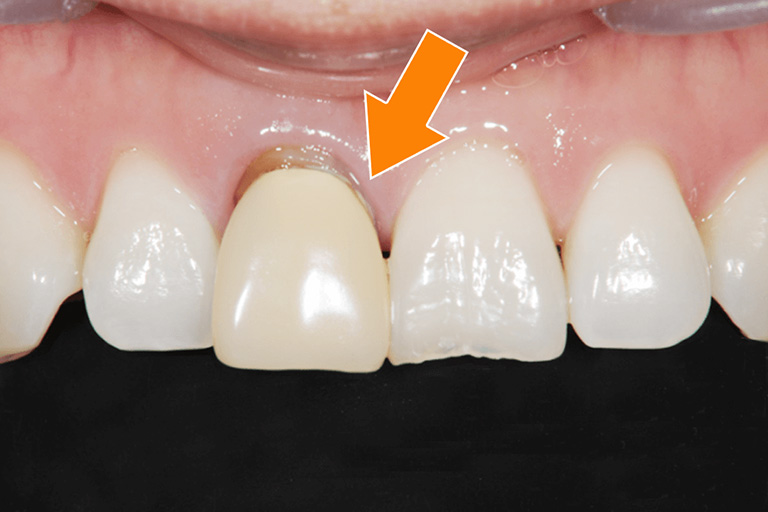

図1

矢印に示す位置に人工物が詰められており、ホワイトニングをしてもこの部分のみ漂白されず、目立ってしまいます。この場合は、ホワイトニング後に治療をし直す必要があります。